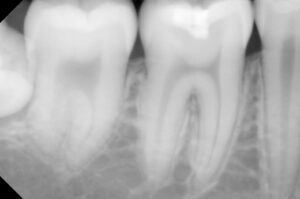

小さいレントゲンで確認し、明らかに進行が

痛みを訴えている歯よりも問題が大きいと

確認出来このままでは歯が割れて崩壊する

同年の10月に検診で来られたときの右上第一大臼歯の

虫歯の状態の写真が緊急を要する感じに見え

再度レントゲンで確認すると、神経を処置しな

ければという状態になってきていることを確認

その時に確認のレントゲンを撮り見るなり

レントゲンで虫歯の確認をするもさほど・・

それより処置した歯が気になったので

レントゲンを撮って痛みが無かった理由を確認

という答えに安堵し、念のためにレントゲンを撮り